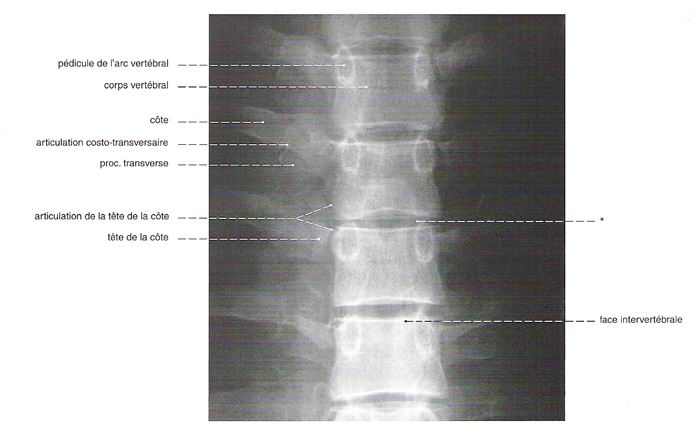

Commençons par le cervical, la suite viendra. Rachis cervical : radiographie, incidence antéro-postérieure

Rachis cervical:  Rachis dorsal: Rachis dorsal:  Rachis lombaire: Rachis lombaire:   1. Processus articulaire supérieur 2. Pédicule droit 3. Processus transverse droit 4. Isthme 5. Processus articulaire inférieur 6. Lame opposée 7. Processus transverse opposé 8. Epineuse 9. Interligne articulaire postérieure 10. Processus articulaire inférieur opposé 11. Processus articulaire supérieur opposé Pour ce qui est de la radioanatomie; nous te laissons le soin d'apprendre tout cela grâce aux livres à ta disposition et à tes stages surtout!  Nous avions commencé une liste de livres de radiologie; à toi de t'en servir et bonnes recherches! Si tu souhaites trouver d'autres correspondances, si quelques détails t'interpellent n'hésite pas à poser des questions précises! Bon courage la marmotte!